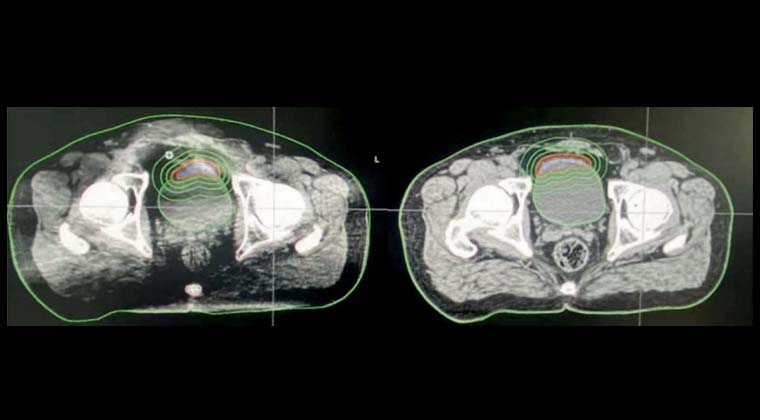

Пациент мужского пола, 67 лет

Диагноз: Рак мочевого пузыря

Сложность лечения: Положение опухоли изменяется в зависимости от наполнения мочевого пузыря, высокая вариабельность между сеансами

Преимущество онлайн-адаптивной радиотерапии Ethos: Перед каждой процедурой используется iCBCT для получения текущего положения мочевого пузыря и опухоли. Затем выполняется повторное контурирование целевой зоны и переработка плана лечения, что делает терапию более точной.

Изображения: МРТ до лечения, МРТ после лечения, контурирование цели во время адаптивной радиотерапии Ethos:

До лечения:

Во время лечения:

После лечения: